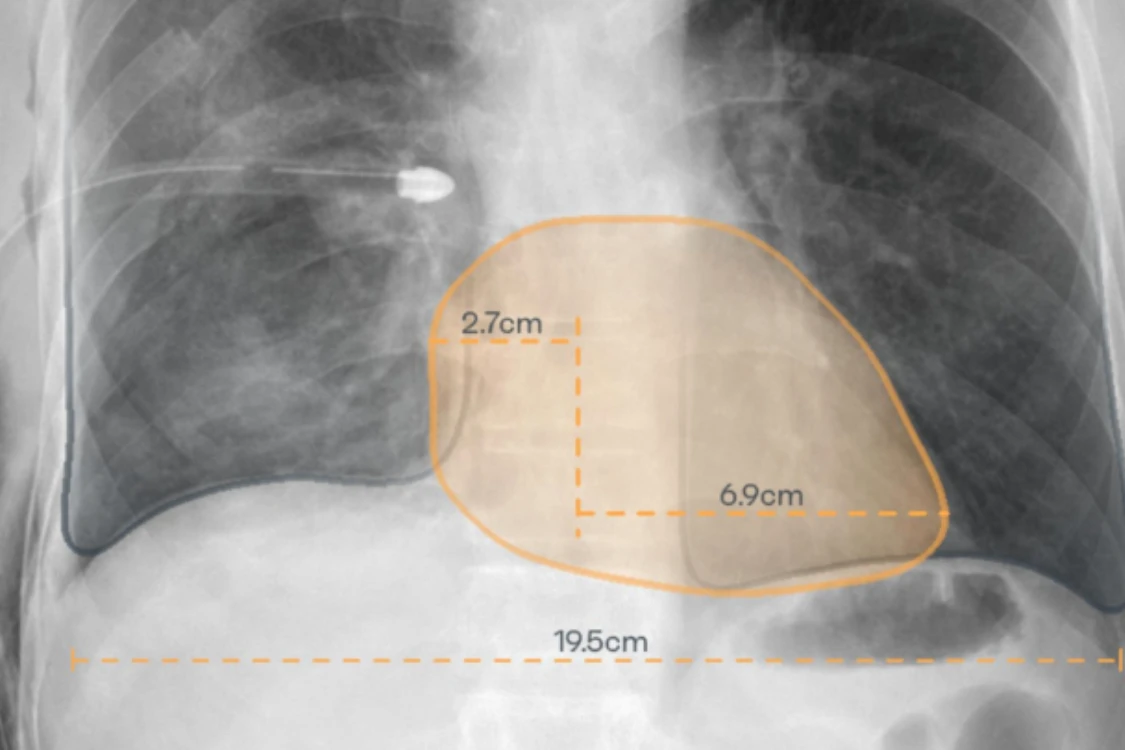

CARDIO-THORACIC INDEX

CASE PRIORITIZATIONRAYSCAPE CXR AI brings computational clarity to everyday imaging, continuously analyzing chest X-rays to surface clinically meaningful patterns that might otherwise remain buried in visual complexity. By combining broad abnormality detection with advanced image enhancement, the system helps transform raw imaging data into structured, actionable insight.